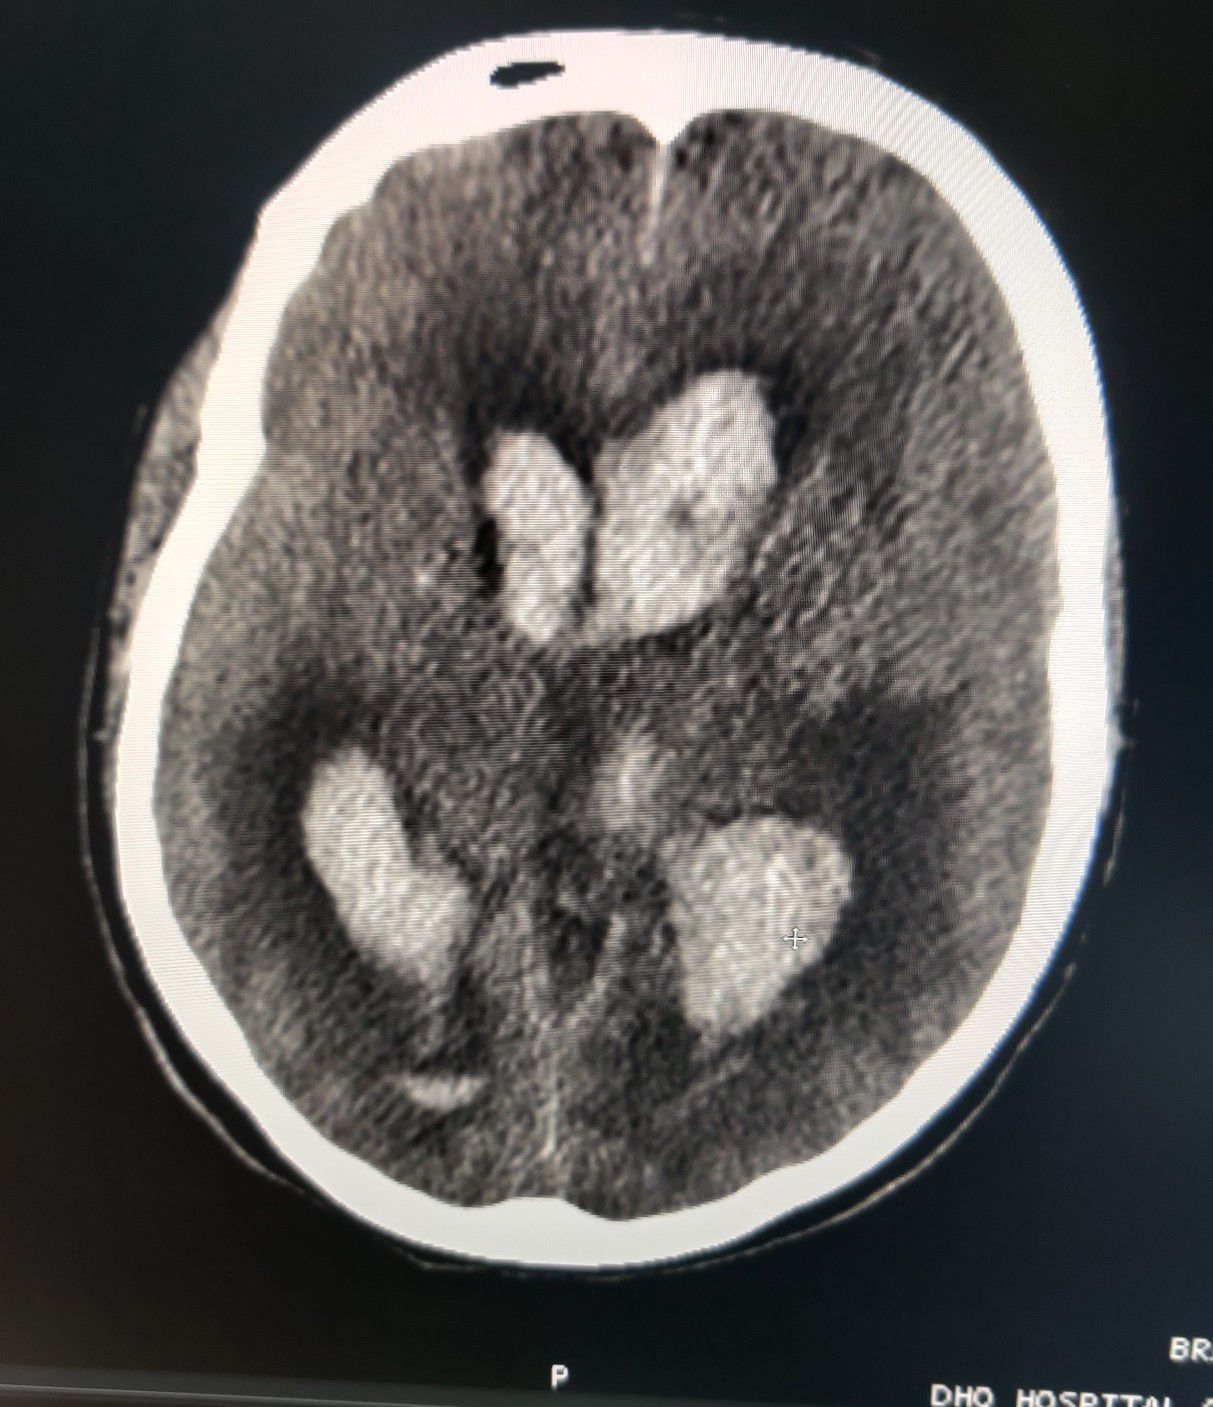

Massive Hemorrhagic CVA

Stroke

Cva

Hemorrhagic